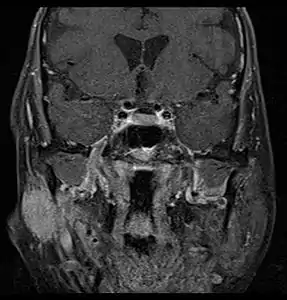

Primary treatment for this cancer, regardless of body site, is surgical removal with clean margins. This surgery can prove challenging in the head and neck region due to this tumor's tendency to show a perineural discontinuous growth, meaning that it follows nerves and different "nests" of the tumor can exist without a connection to the original tumor. Therefore, MRI-images should be analysed following nerve tracts up to the brainstem. Adjuvant or palliative radiotherapy is commonly given following surgery. For advanced major and minor salivary gland tumors that are inoperable, recurrent, or exhibit gross residual disease after surgery, fast neutron therapy is widely regarded as the most effective form of treatment.[13][14][15][16] Chemotherapy is used for metastatic disease. Chemotherapy is considered on a case-by-case basis, as data on the positive effects of chemotherapy are limited. Clinical studies are ongoing, however.

Coronal MRI showing right parotid adenoid cystic carcinoma with perineural spread of tumor: The tumor originates in the right parotid gland and spreads along the trigeminal nerve via the auricuotemporal branch extending intracranially through the foramen ovale at the skull base towards Meckel's cave.

Coronal MRI showing right parotid adenoid cystic carcinoma with perineural spread of tumor: The tumor originates in the right parotid gland and spreads along the trigeminal nerve via the auricuotemporal branch extending intracranially through the foramen ovale at the skull base towards Meckel's cave. Coronal MRI showing right parotid adenoid cystic carcinoma with perineural spread of tumor along the facial nerve extending to the stylomastoid foramen